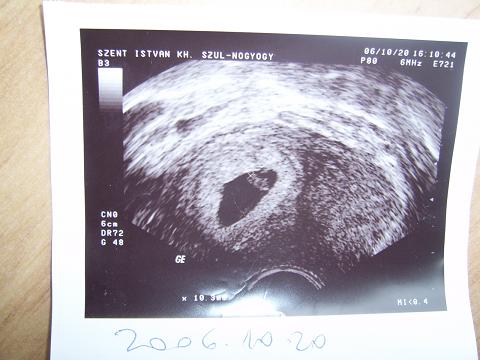

Ha minden igaz, itt láthatjátok a 6-7. héten készült képet. Ki tudja, hogy, hogy nme, ez alapján még nem kezdődött el a találgatás a családban, kire hasonlít a pici. :D